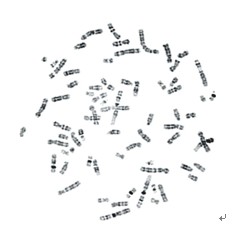

BandView染色體條帶分析系統

型號:BandView

詢價:400-0630-558

廣州市深華提供的 BandView染色體條帶分析系統 質量過硬,物美價廉。如需服務請點擊右側在線客服,也可以直接致電我們,400-0630-558,18819137158,我們將會竭誠為您服務!